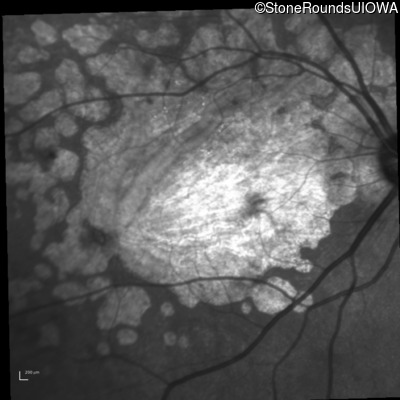

Infrared Fundus Photograph - Right - 20/63

Exemplar